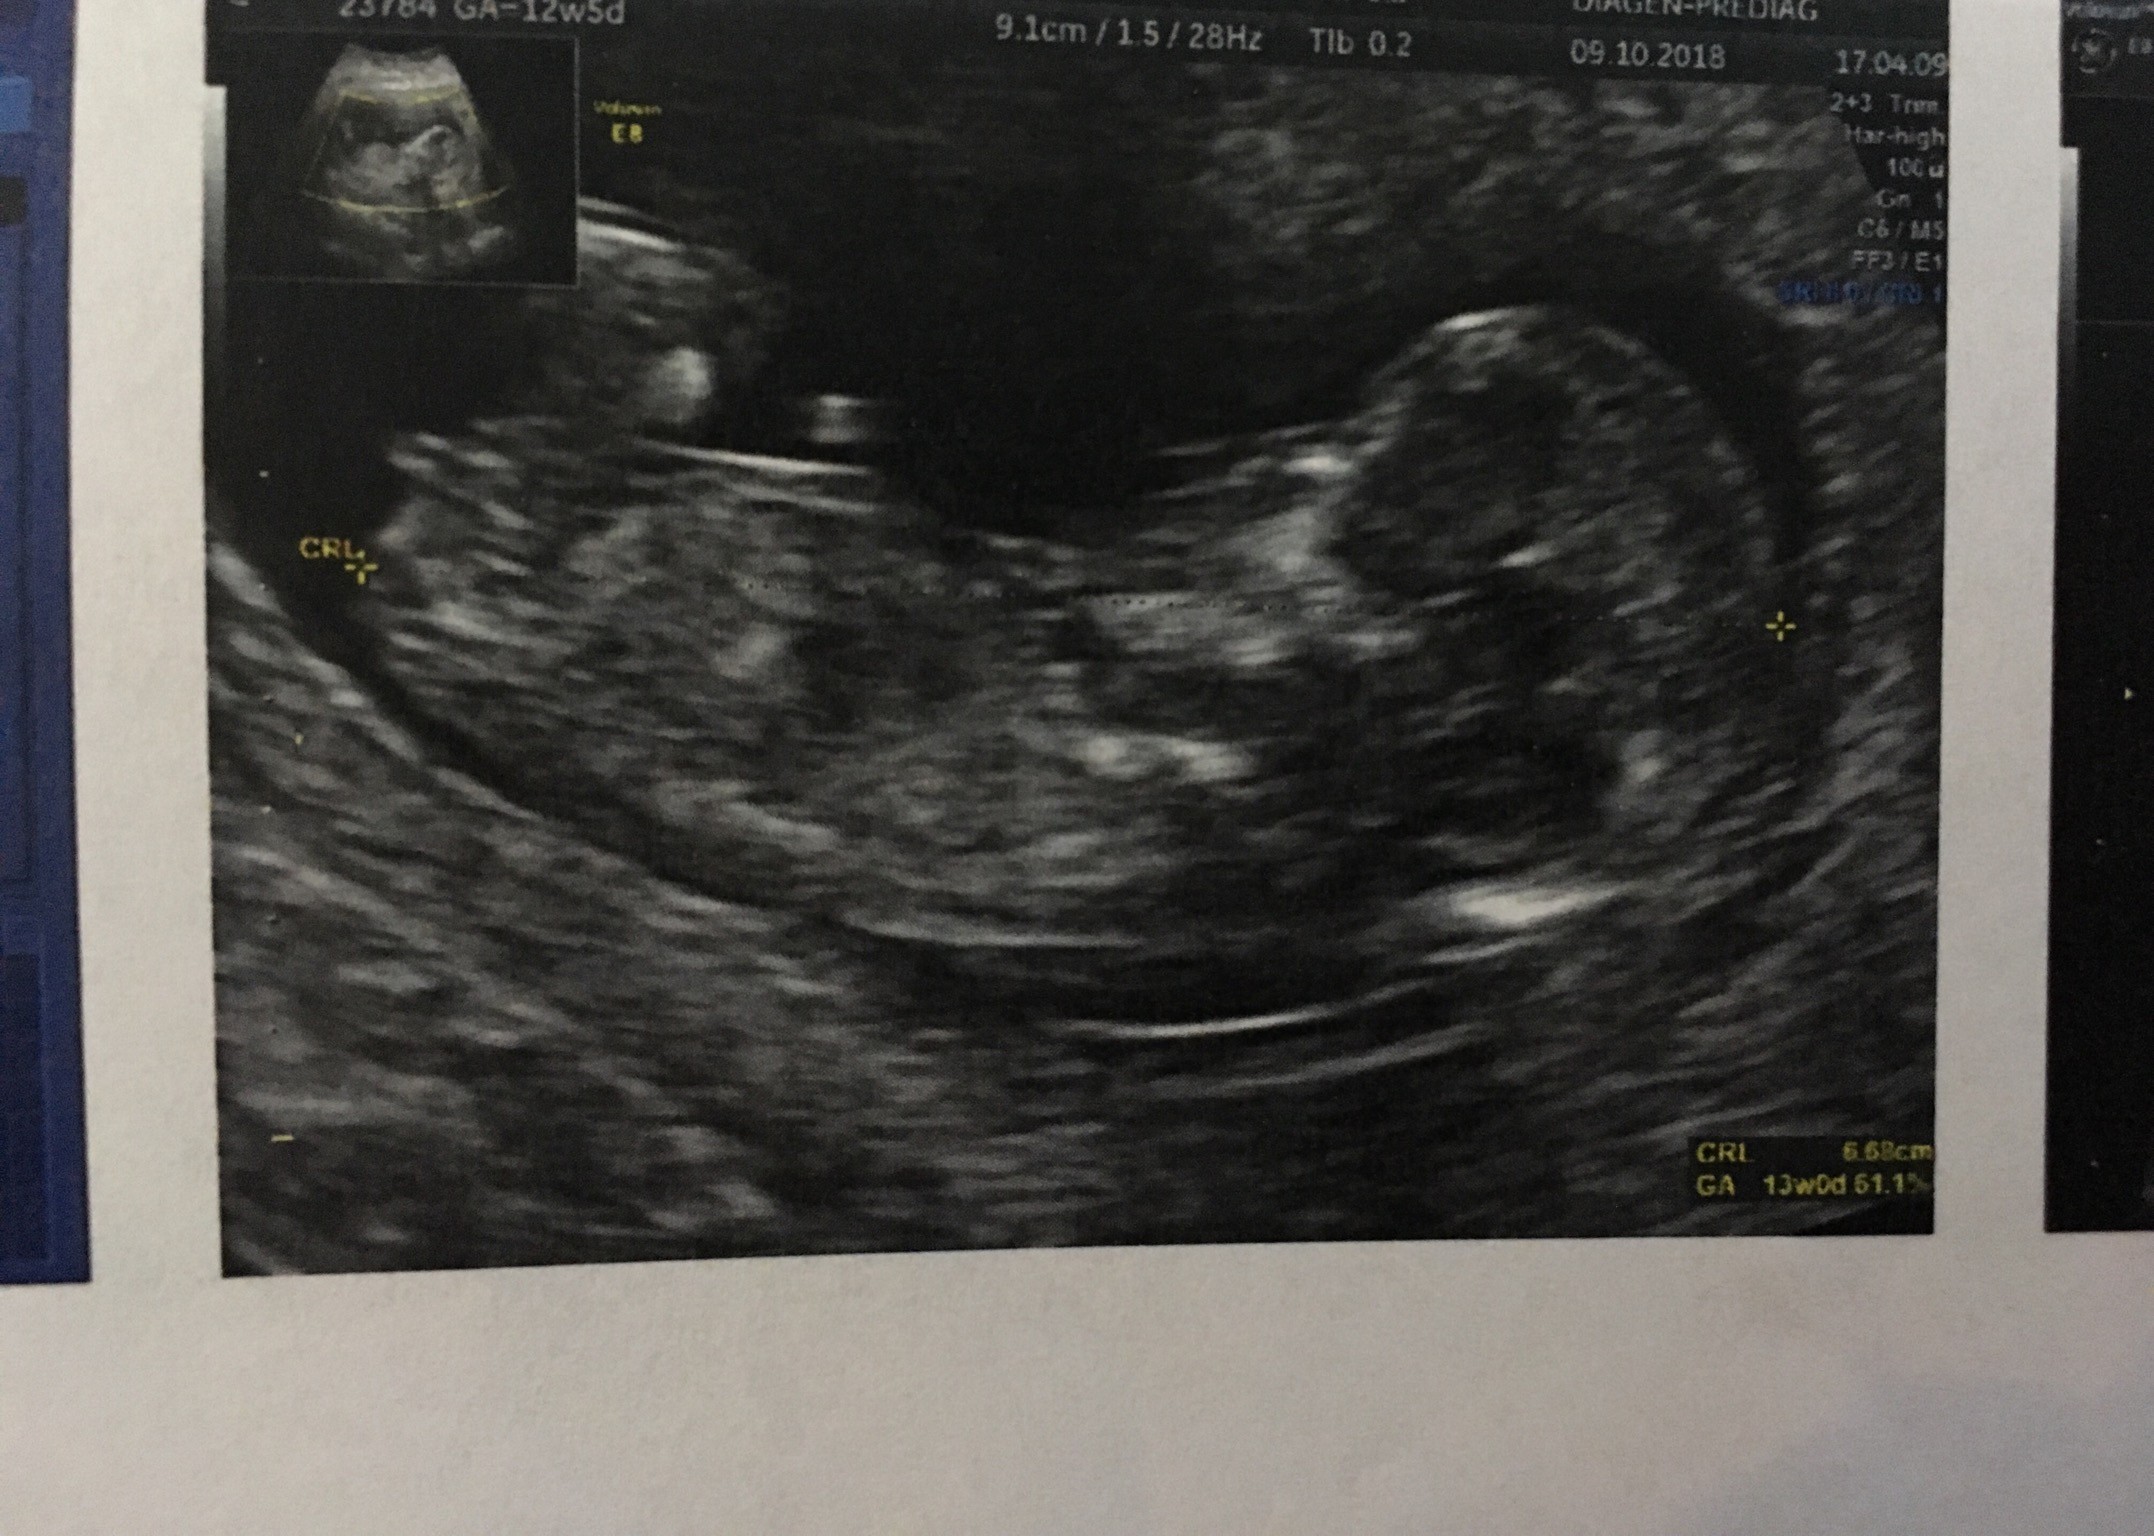

W oczekiwaniu na wynik USG wskazujący na płeć Twojego dziecka pamiętaj że maluchy nie zawsze chcą współpracować. Witam mam pytanie w którym tygodniu ciąży można rozpoznać płeć dziecka. Czasami udaje się określić płeć dziecka w badaniu USG już w 12-13 tygodniu ale w wielu przypadkach jest to badanie w 20 tygodniu.

Lekarz tłumaczy kiedy najłatwiej rozpoznać płeć dziecka Według wytycznych nie zaleca się determinacji płci płodu przed 12 tygodniem ze względu na niską skuteczność 54. Może jest jeszcze za wcześnie by móc poznać płeć dziecka dzięki badaniu. Niektóre kobiety już nieco wcześniej mogą zostać poinformowane o płci dziecka a inne później.

Obecnie odpowiedź na to pytanie dają badania USG. Płeć dziecka na USG rozpoznawana jest już po 16 tygodniu ciąży ale badanie w tym czasie nie daje pewności. Jest to spowodowane ułożeniem płodu.

Tygodniu ciąży plusminus 2 tygodnie. Dlatego większość lekarzy wstrzymuje się z odpowiedzią do 20 tygodnia kiedy to dokładnie widać wargi sromowe w przypadku dziewczynki oraz penisa i mosznę u chłopca. Współczesna nauka nie potwierdza tej tezy.